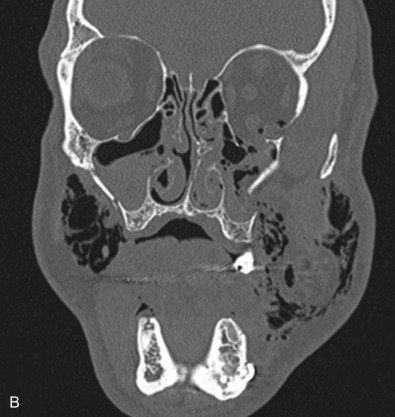

The gold standard for radiographic evaluation is thin-slice helical computed tomography (CT). Midface fractures are confirmed by axial, coronal, and sagittal views. The degree of comminution, bone loss, and detailed images of the fracture patterns can be assessed and juxtaposed to surrounding soft tissue structures. 3D reconstruction, when utilized, can aid in visualizing the complex 3D anatomical orientation of fracture fragments that occur in Le Fort injuries and facilitate reconstructive planning.

Le Fort II fractures are pyramidal in shape, involving the central portion of the midface while the lateral orbits and zygoma remain intact. The line of fracture extends bilaterally through the nasofrontal junction, medial orbital wall, inferior orbital rim, along the maxilla, through the dental alveolus anteriorly and posteriorly at the level of the maxillary tuberosity into the pterygoid plates ( Figs. 1.13.14 and 1.13.15 ). Only Le Fort II fractures violate the inferior orbital rim, causing the highest incidence of infraorbital nerve hypesthesia due to the proximity to the infraorbital foramen. Bones of the maxilla below the Le Fort II line of fracture can be intact, however they are often comminuted with other fracture patterns occurring in the Le Fort II segment. The force is typically delivered centrally at the level of the nasal bones, resulting in the separation of the central maxilla from the surrounding facial skeleton. Brain injuries are more frequent in central Le Fort II injury patterns.